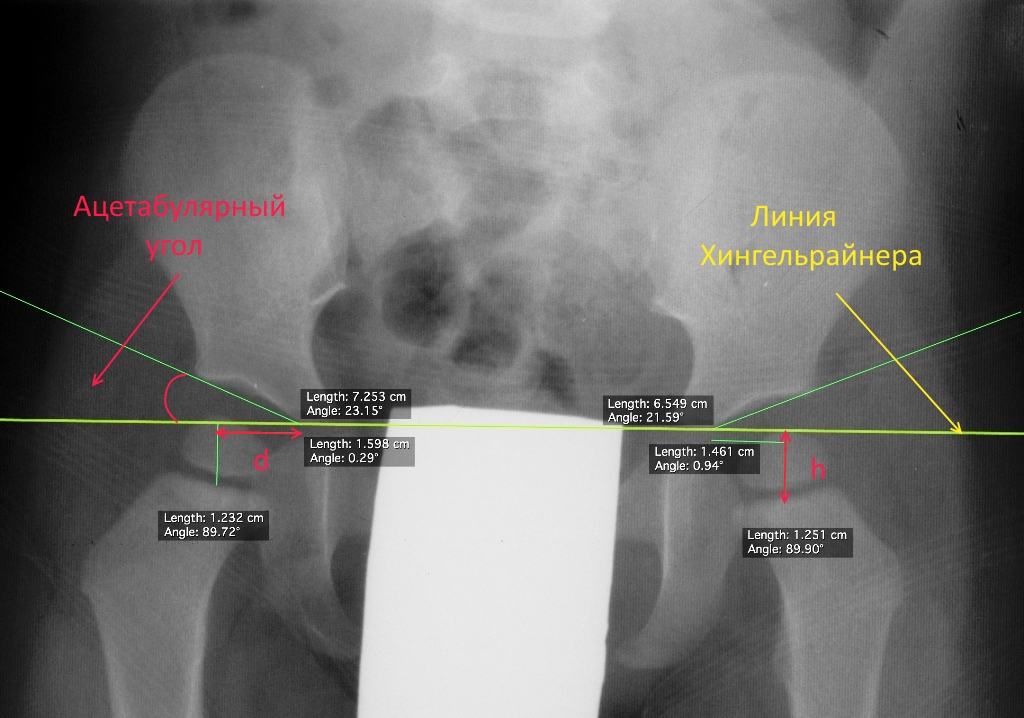

цетабулярные углы у детей таблица

Ацетабулярные углы у детей таблица 56 фото